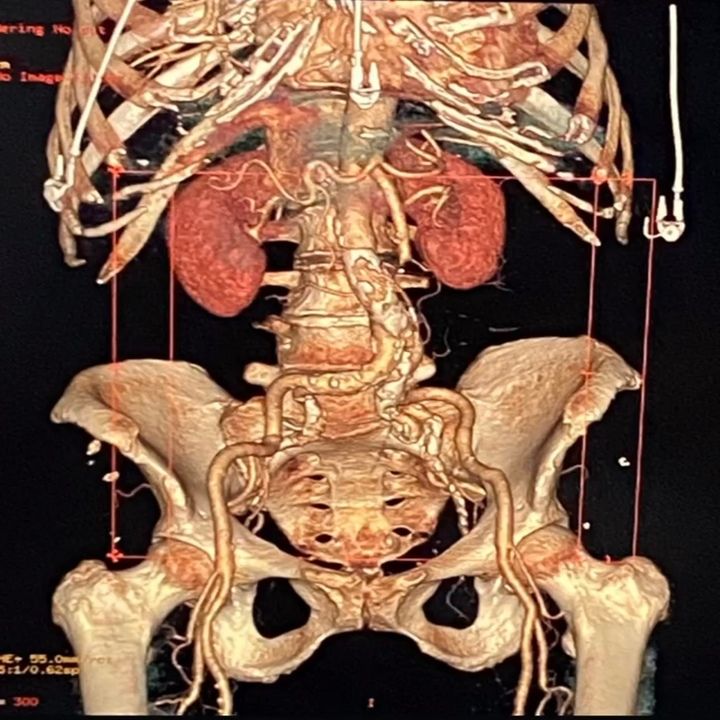

• Cirugía arterial

• Cirugía endovascular

• Diagnóstico vascular no invasivo